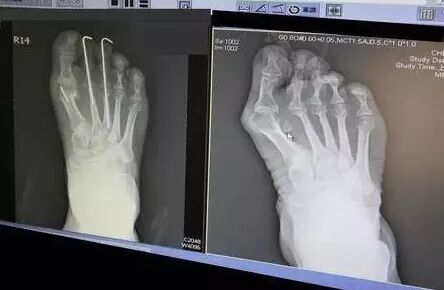

对“高挑”和高跟鞋的执念,让她的脚已经畸形,脚拇指外翻。医生警告她:再穿高跟就不能走路了。

好在她想开了,于是我们终于看到贝嫂换上了平底鞋。